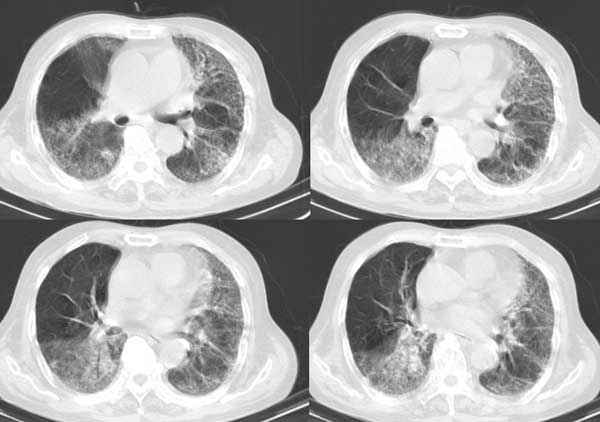

以下是引用dalianren在2006-7-20 21:23:00的发言:[br]我考虑是肺泡蛋白沉积症:典型表现为两肺内散在片状\"磨玻璃\"样混浊区呈地图样分布.

以下是引用lj0804在2006-7-21 12:57:00的发言:[br]支持[br]我考虑是肺泡蛋白沉积症:典型表现为两肺内散在片状\"磨玻璃\"样混浊去呈地图样分布.